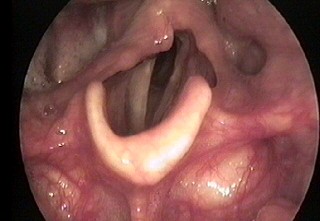

Vocal cord paralysis refers to restricted movement of the vocal cords caused by dysfunction of the nerve(s) responsible for sending signals to the vocal cord muscles. Depending on how many cords are affected, the paralysis may be unilateral (one-sided) or bilateral (both sides).

Normally, the vocal cords open during breathing and close completely during speaking, singing, or swallowing.

Diagnosis is made by examining the vocal cords with videolaryngostroboscopy or flexible fiberoptic laryngoscopy. The impact of paralysis on the voice can be evaluated using acoustic voice analysis, while laryngeal EMG (electromyography) provides information about whether nerve damage is reversible.